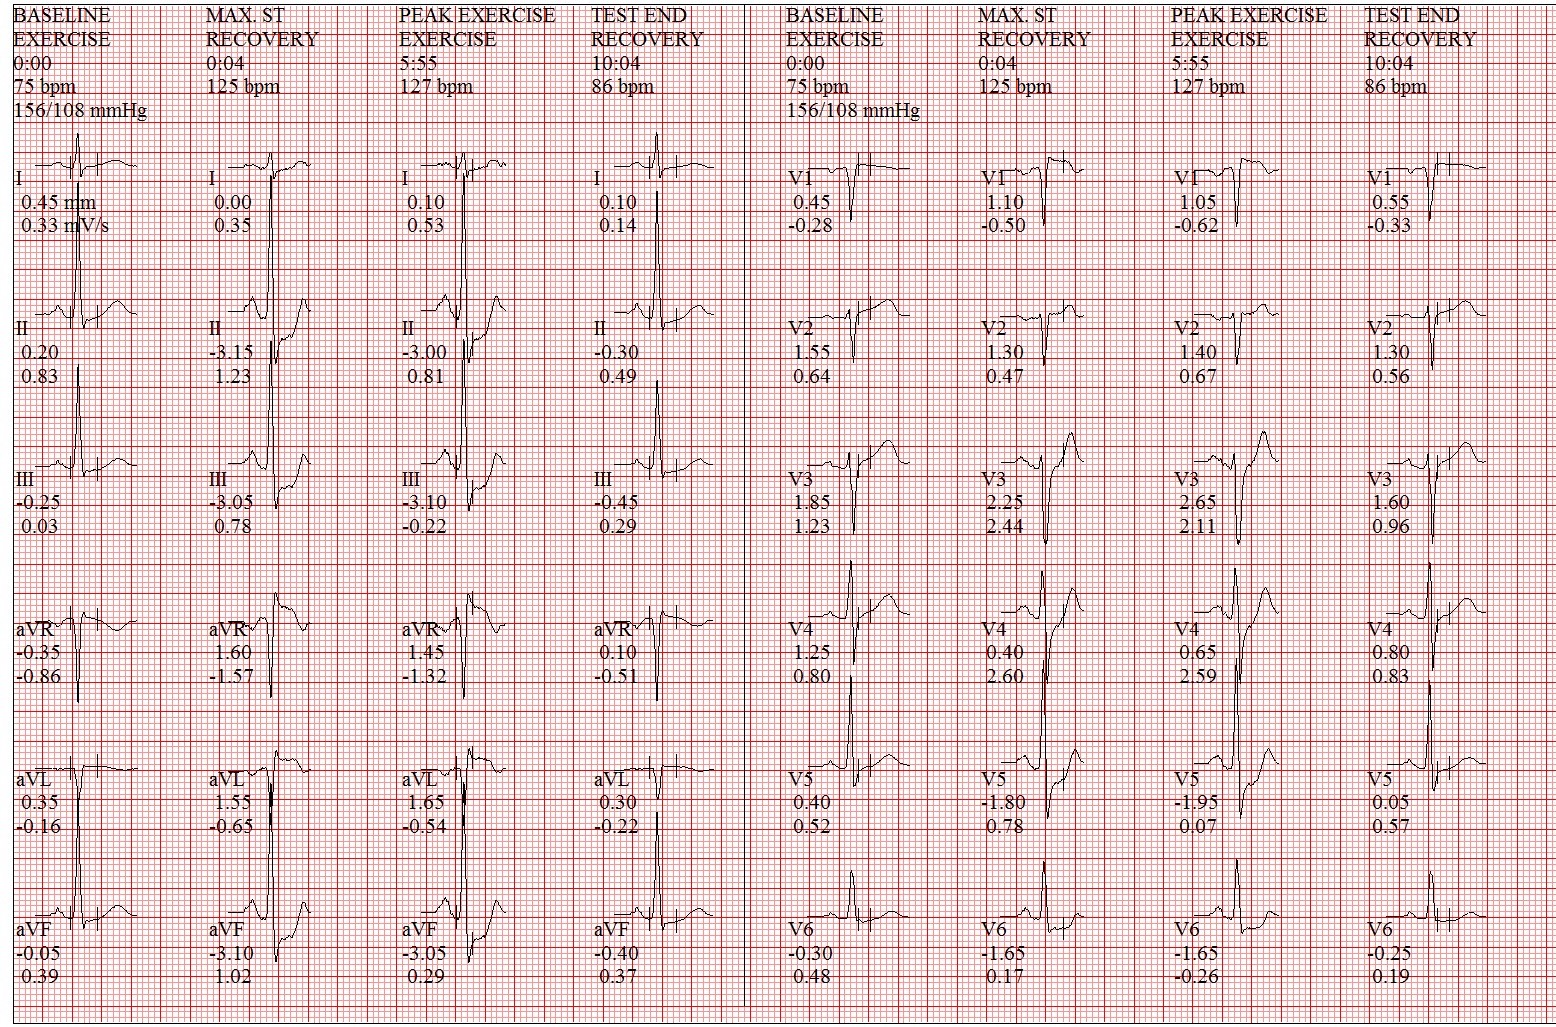

Treadmill's exercise ECG was performed, and showed ST depression over inferior and lateral leads. The exam was terminated before 90% predicted heart rate achieved(Bruce stage 2) due to dyspnea and the patient cannot follow up. Echocardiogram was also arranged, and showed mild AR, TR, mild to moderate MR and normal LV systolic wall motion with LVEF 55%. Chest X ray found no definite evidence of significant active lung lesion or cardiomegaly.